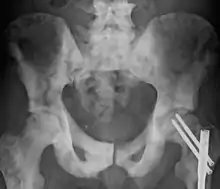

Sclerosis of the bones of the pelvis due to prostate cancer metastases

Osteosclerosis is a disorder that is characterized by abnormal hardening of bone and an elevation in bone density. It may predominantly affect the medullary portion and/or cortex of bone. Plain radiographs are a valuable tool for detecting and classifying osteosclerotic disorders.[1][2] It can manifest in localized or generalized osteosclerosis. Localized osteosclerosis can be caused by Legg–Calvé–Perthes disease, sickle-cell disease and osteoarthritis among others. Osteosclerosis can be classified in accordance with the causative factor into acquired and hereditary.[2][1]

Osteosclerosis can be detected with a simple radiography. There are white portions of the bone which appear due to the increased number of bone trabeculae.